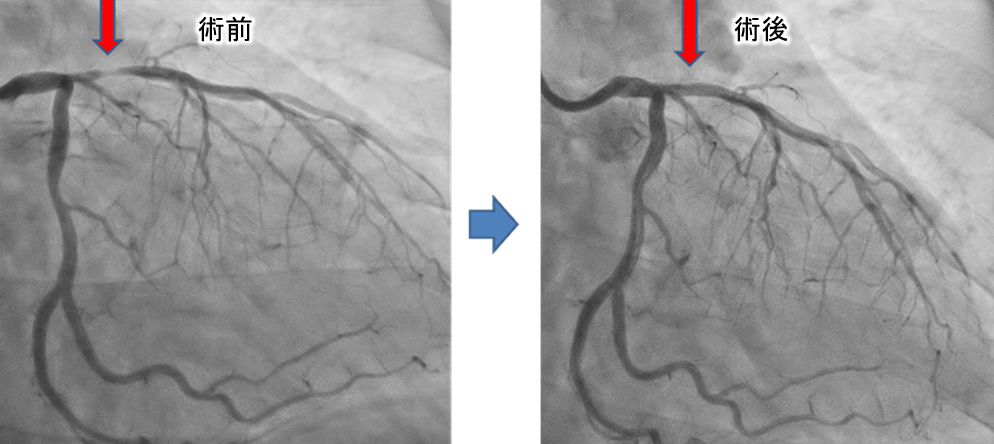

以下は当院で施行したDCAの症例です。赤矢印の部分に狭窄がありましたが、DCAで削り取ることで、ステントを留置することなく治療を終えました。術後数年経過しますが、再狭窄なく病状は安定しております。

症例紹介

症例患者様:60歳代 男性

症例治療内容:DCA(方向性冠動脈粥腫切除術)にてプラーク切除後に薬剤溶出性バルーンで拡張し良好に開大した。

症例治療回数:1回